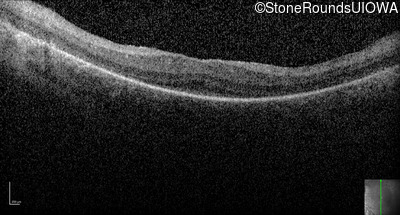

Optical Coherence Tomography - Right -

No Light Perception

Exemplar

Expanded OCT Stack

×